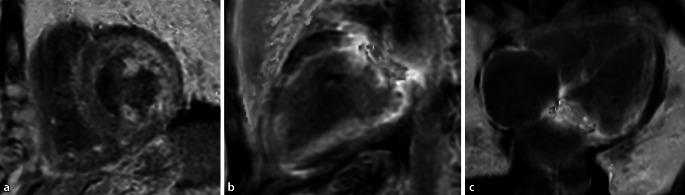

The strength of MRI is the ability to differentiate nonischemic cardiomyopathies from other diseases with similar morphofunctional aspects, based on the possibilities of tissue differentiation. In the case of dilated cardiomyopathy (DCM), for example, a differentiation from inflammatory DCM is possible. In the case of hypertrophic cardiomyopathy (HCM), obstructive and nonobstructive forms can be differentiated analogously to the echo but amyloidosis or Fabry disease can also be detected. Evaluation of the right ventricular function is reliable in arrhythmogenic right ventricular cardiomyopathy (ARVC). The use of MRI is also able to directly detect the characteristic fibrofatty degeneration. In the rare restrictive cardiomyopathies (RCM), MRI can track restriction and, for example by means of T1, T2 and T2* mapping, detect sphingolipid accumulation in the myocardium in the context of Fabry disease or iron overload in the context of hemochromatosis.

MRI的优势在于能够基于组织分化的可能性,将非缺血性心肌病与形态功能方面相似的其他疾病区分开来。例如,对于扩张型心肌病(DCM),可以与炎症性DCM进行区分。对于肥厚型心肌病(HCM),梗阻性和非梗阻性形式可类似于超声心动图进行区分,同时也能检测出淀粉样变性或法布里病。在致心律失常性右室心肌病(ARVC)中,对右室功能的评估是可靠的。MRI的应用还能够直接检测到特征性的纤维脂肪变性。在罕见的限制型心肌病(RCM)中,MRI可以追踪限制情况,例如通过T1、T2和T2* 成像,在法布里病的背景下检测心肌中的鞘脂蓄积,或在血色素沉着症的背景下检测铁过载。